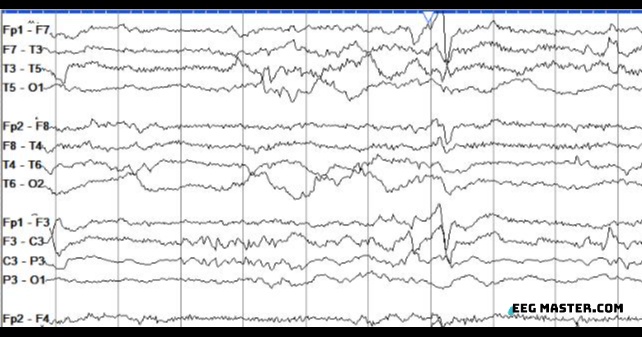

62M in coma after cardiac arrest. Which of the following is correct regarding this EEG.

A. B/l synchronous activity.

B. Unilateral LPDs.

C. Electrographic seizures occur in 10%.

D. Reliable predictor of poor outcome.

E. Good outcome possible.